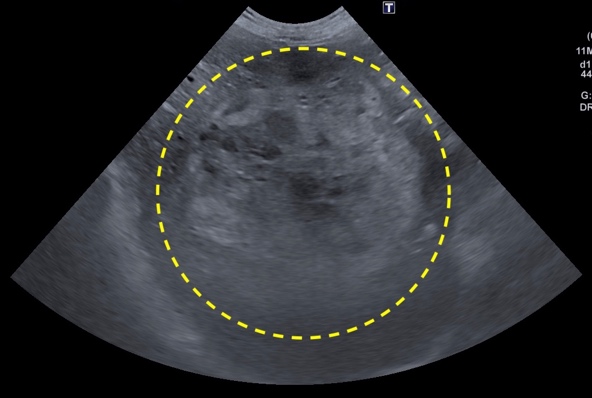

腎臓腫瘍

血尿や腹部の腫れ、腹部の不快感などを示します。

犬では腺癌が最も多く認められる腫瘍で、猫ではリンパ腫の発生が多い。

片側の腎臓腫瘍で、転移性所見のない症例では外科的摘出手術が適応になります。